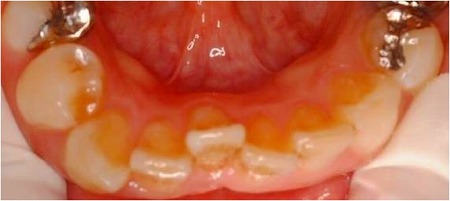

歯を根ごと動かす本来の意味での矯正で、1本だけとか○本だけとかを動かす事はほとんど不可能です。なぜなら、歯は隣の歯と接しているので隣が動かないのに、動かせません。また上下の歯は咬み合っていますから、上の歯だけとか下の歯だけとかを動かせません。だから上の歯だけの矯正とか、下の歯だけの矯正なども、上下がきちんとかみ合っていない場合しかできないのです。写真は下の前歯だけの部分矯正した方です。

初診時